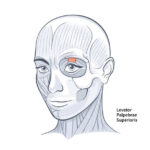

ATL-131 HALF MUSCULAR HEAD WITH VESSEL SOFT

Life size model shows the right half of the human head and neck, sectioned along the sgittal plane. A superficial dissection exposes the facial muscles, the superficial blood vessels and nerve branches of the face and scalp, the parotid and submandibular glands. A median dissection expose the brain with its internal structure, tha pharynx and upper respiratiry tract, a section of the cervical vertebrae.